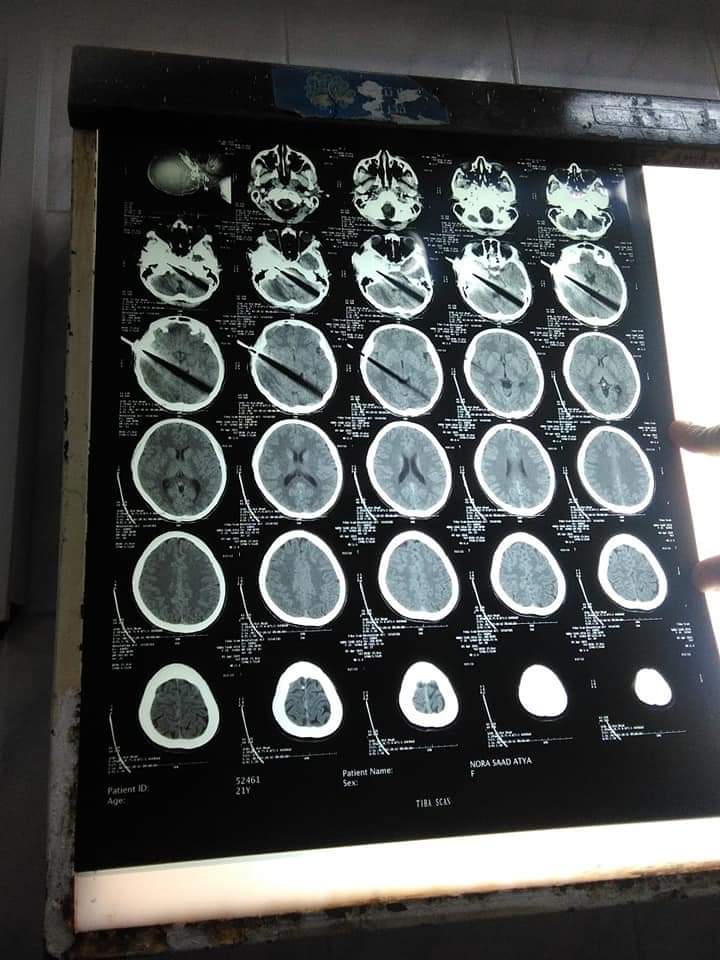

تمكن الفريق الطبي بمستشفى "شبين الكوم" التعليمي بمحافظة المنوفية، اليوم الثلاثاء، من إنقاذ حياة سيدة تعرضت لضربة بسلاح أبيض "سكين" في رأسها.

ونجح الفريق الطبي، برئاسة الدكتور إسلام العربي، وإشراف الدكتور محمد موسى، من استخراج السكين، فيما لا تزال السيدة تحت الملاحظة بالعناية المركزة بالمستشفى.